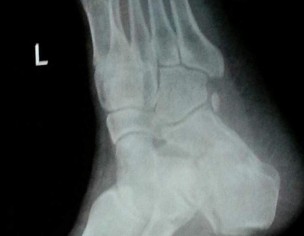

My father fell off from height 3 weeks back and got his left calcaneus fractured. We saw a doctor the same day who applied plaster cast on his foot and adviced icing and foot elevation Later, we saw another doctor who adviced cast removal immediately and starting physiotherapy and exercises. The latter also said that cast should not have been applied in this particular case. Also, the cast application on the same day of fracture could cause ischemia due to impending swelling.

this fracture need surgery for better functional outcome

This needs surgery